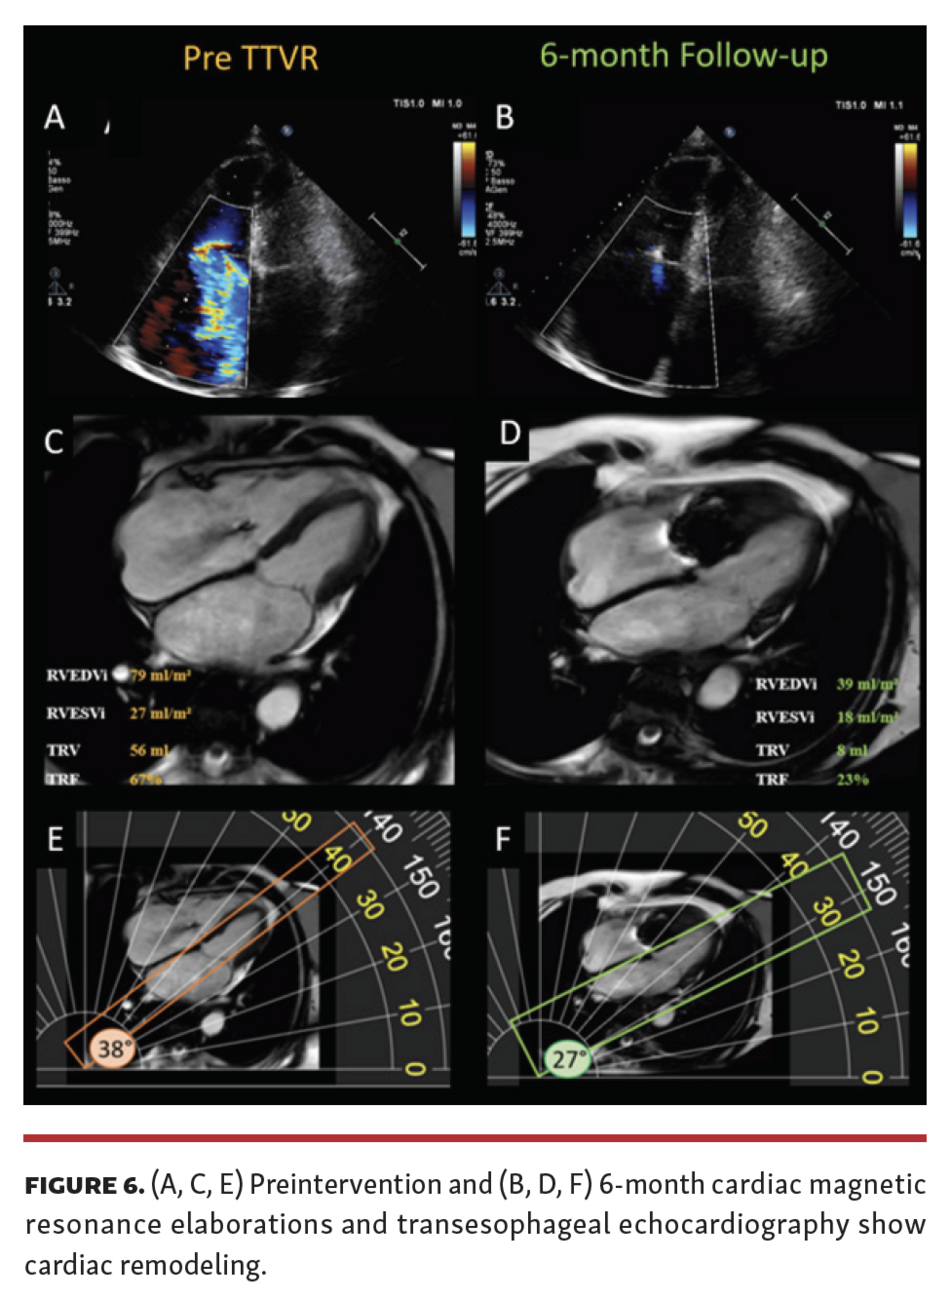

The preprocedural cardiac magnetic resonance (CMR) showed a right ventricular end-diastolic volume index (RVEDi) of 79 mL/m2, right ventricular end-systolic volume index (RVESi) of 27 mL/m2, tricuspid regurgitant volume (TRV) of 56 mL, and tricuspid regurgitant fraction (TRF) of 67% (Figure 3). Due to the patient's history of breast cancer radiotherapy and high surgical risk, the heart team preferred a transcatheter approach as the treatment option. The first TriClip (Abbott Vascular) was successfully implanted in the anteroseptal commissure, determining annulus size reduction and the subsequent necessity of transesophageal echocardiographic projection change to assess the result due to acute reshaping (Figure 4 and Figure 5; Video Series). A second TriClip was implanted in the anteroseptal commissure, highlighting the changes in the valvular plane and cardiac axis (Video Series). Residual TR was trivial (Video Series). The acute remodeling was confirmed at the CMR follow-up (Figure 6), with significant volume and TR reductions (RVEDi, 39 mL/m2; RVESi, 18 mL/m2; TRV, 8 mL; and TRF, 23%).

This case demonstrates immediate and considerable right ventricular reshaping due to successful TTVR with a sustained result at 6 months in isolated primary TR.